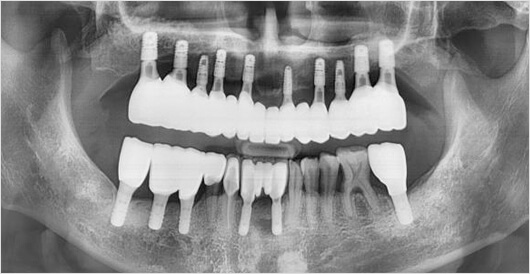

네비게이션 임플란트

0.1mm의 오차도 허용하지 않는 정확함